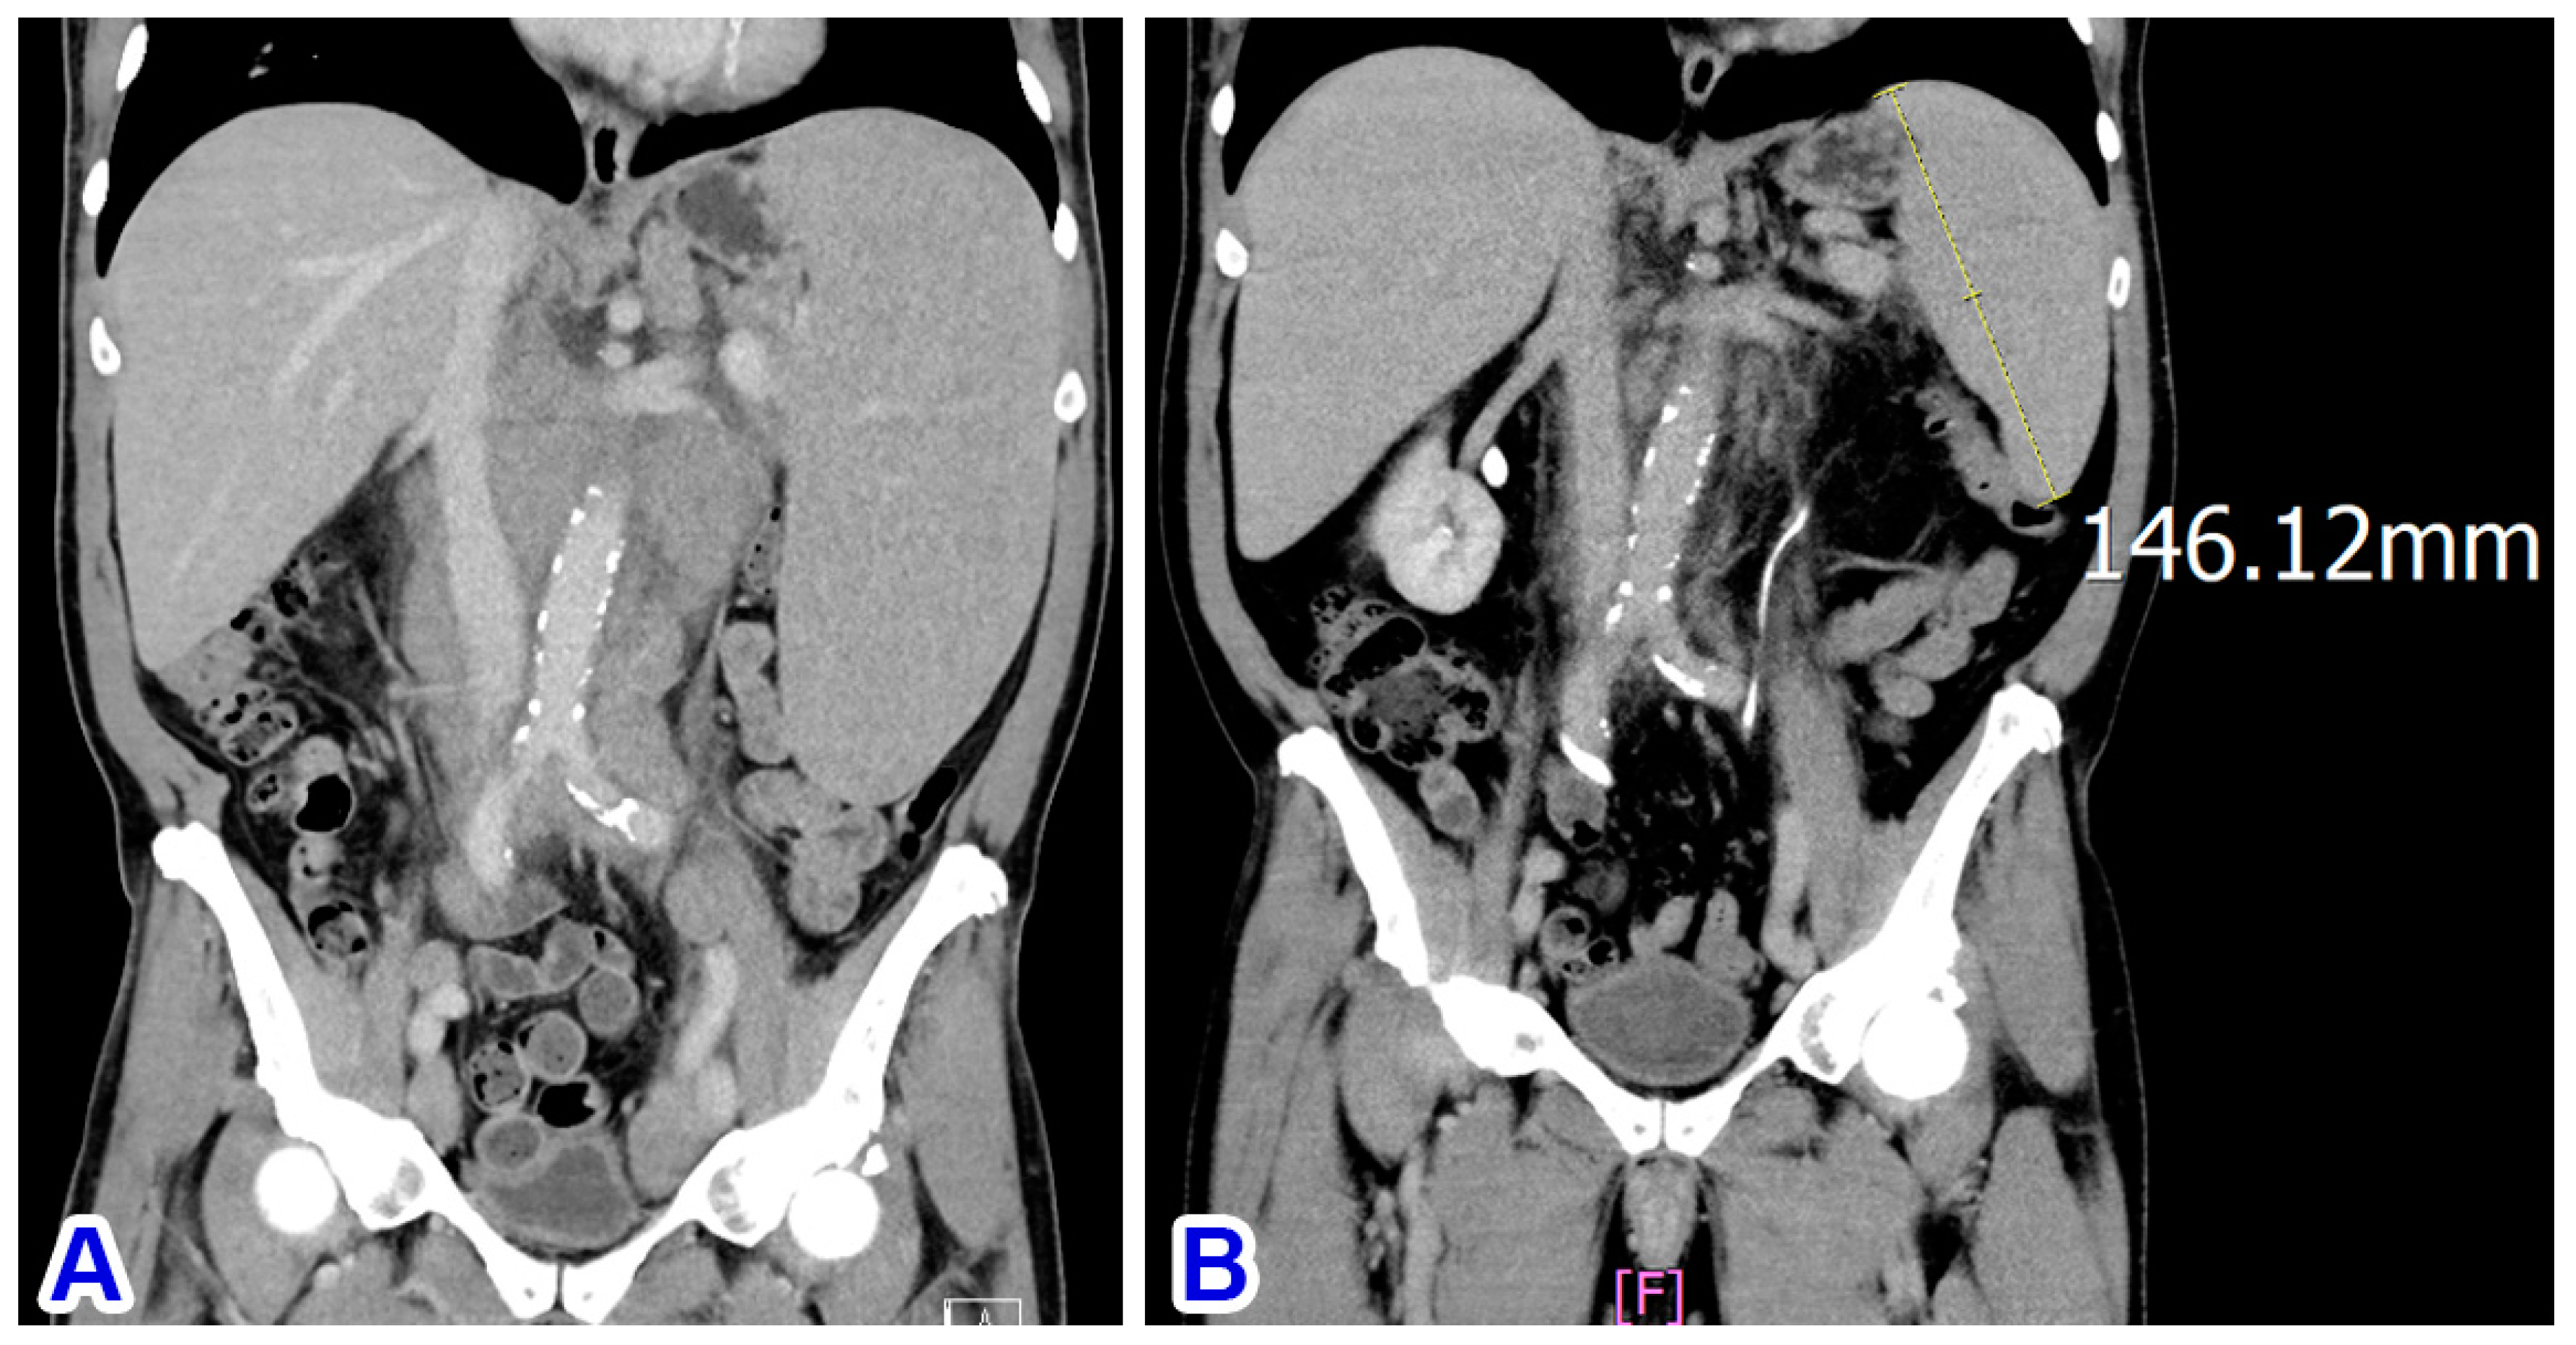

Bone marrow involvement was confirmed by flow cytometry using marrow aspirate. The marrow trephine had nearly 100% cellularity and was diffusely infiltrated by small atypical lymphocytes expressing CD5 (weakly), CD20, and MNDA but not CD23. Subsequent abdominal CT scans showed marked splenomegaly (Figure 3A) and multiple sites of abdominal and pelvic lymphadenopathy, indicating SMZL with stage IV disease, leukemic change, and secondary nodal involvement.

The patient was treated with six courses of rituximab and four courses of cyclophosphamide, vincristine, and prednisone (COP), but he was intolerant to the regimen and developed a severe gastric ulcer with bleeding. Subsequently, the treatment was switched to bendamustine and rituximab (BR; six courses). Abdominal CT scans in November 2023 showed a significant shrinkage of the lymphadenopathy but only a partial shrinkage of the splenomegaly (from 18.6 cm to 14.6 cm; Figure 3B). He was evaluated to have achieved a partial response as of January 2024, 10 months after initial diagnosis. Although a partial shrinkage of splenomegaly may indicate residual disease, long-term management to minimize toxicity is often the goal for patients with such indolent lymphomas. Due to the drawbacks of splenectomy—short-term (perioperative events) and long-term (immune suppression and infections) complications—our clinical team chose active monitoring after discussion with the patient.

Figure 3. (A) CT scan at diagnosis shows marked splenomegaly. (B) Partial regression of the splenomegaly after immunochemotherapy.